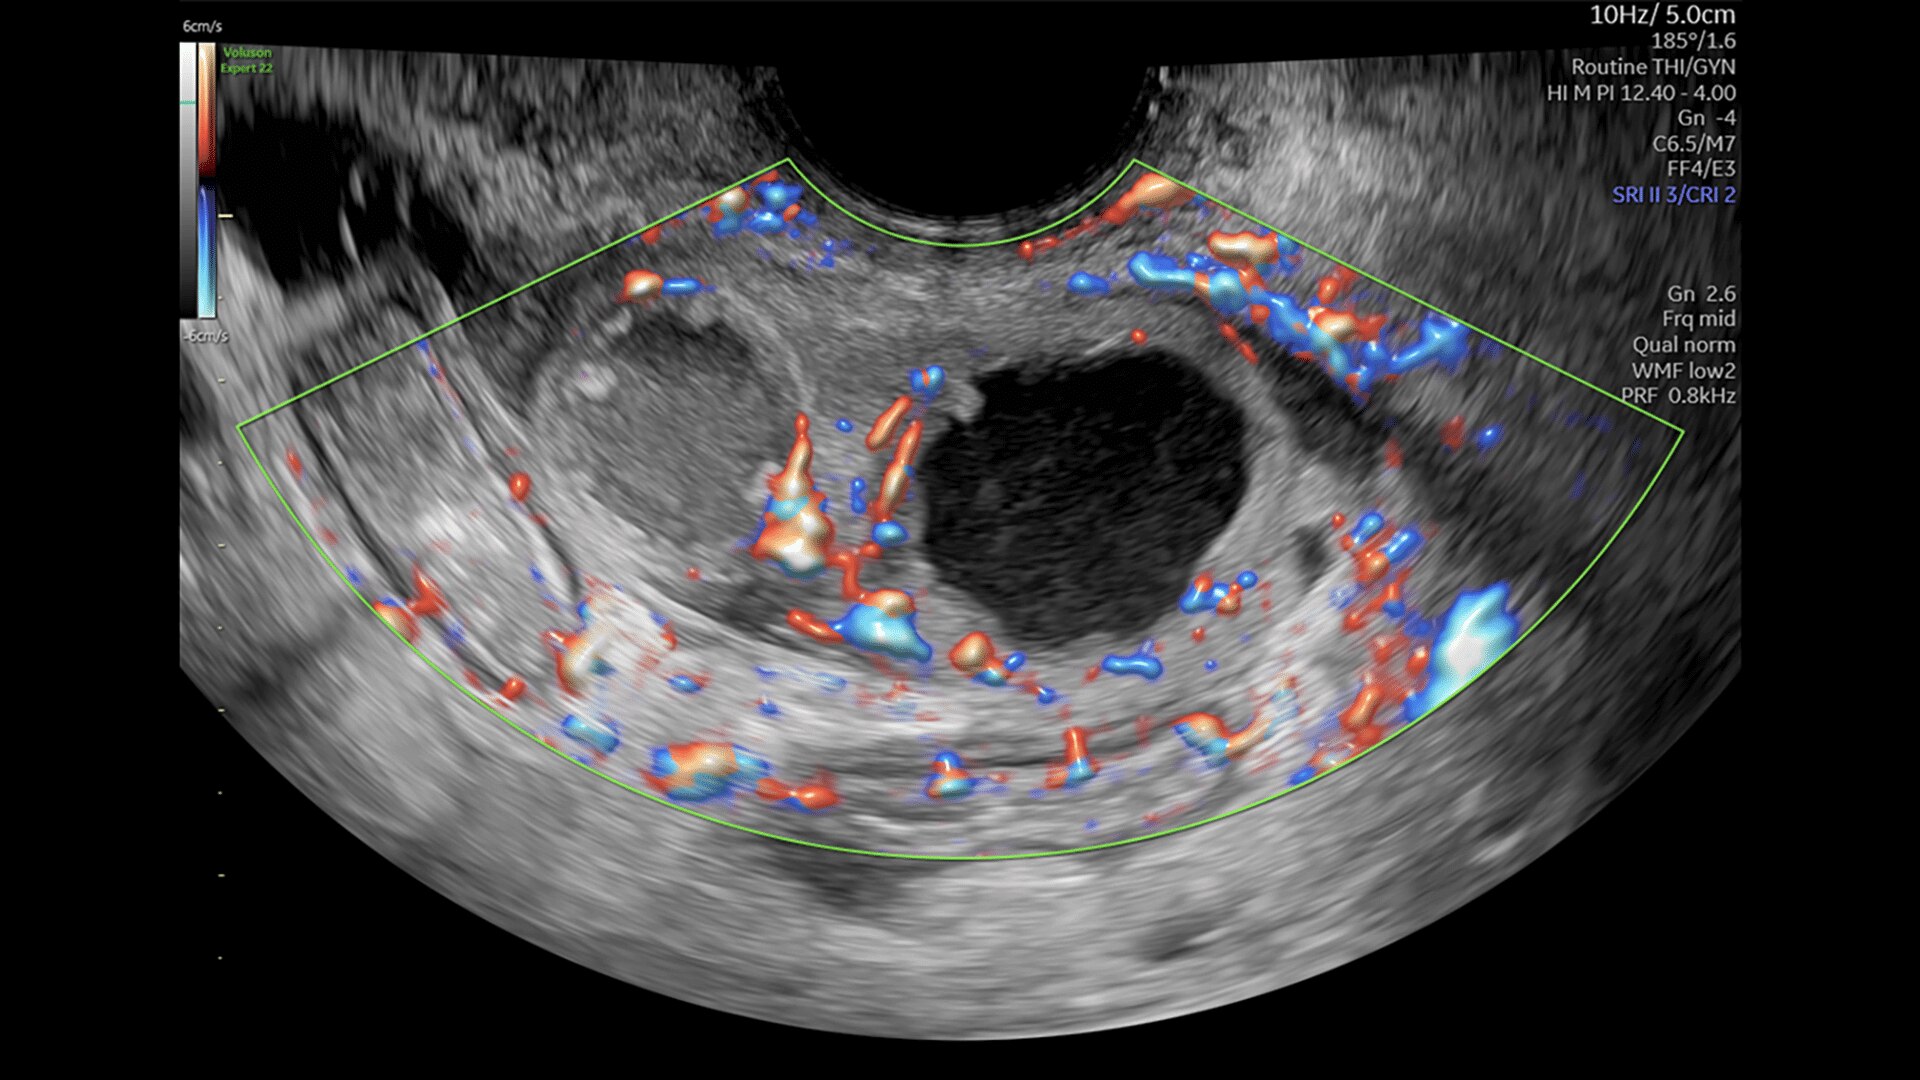

FETAL HEART EVALUATION

Get to the Heart of the Matter

Identifying fetal cardiac abnormalities earlier means you can intervene sooner, plan for delivery, and potentially improve outcomes. The Voluson Expert 22 provides a full solution of progressive tools, to help distinguish the tiniest structures with stunning clarity to provide patient answers faster.